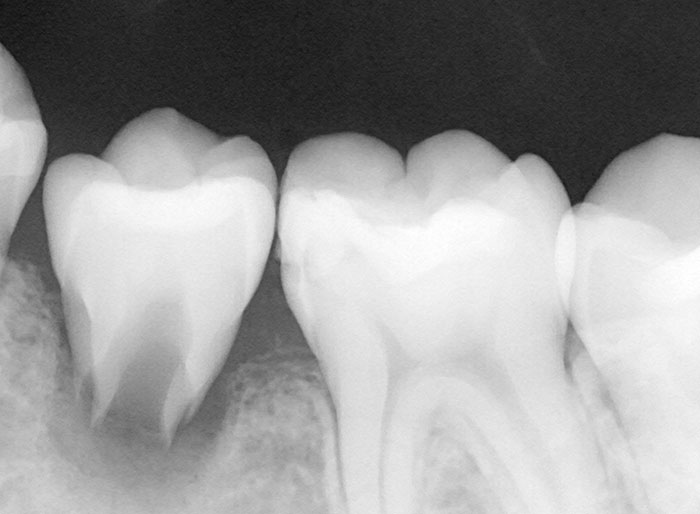

Before

After

左上の親知らずの歯を移植しました。20代前半の症例です。

ご自身の歯のため親和性が高く、移植後も不自由なく機能しています。